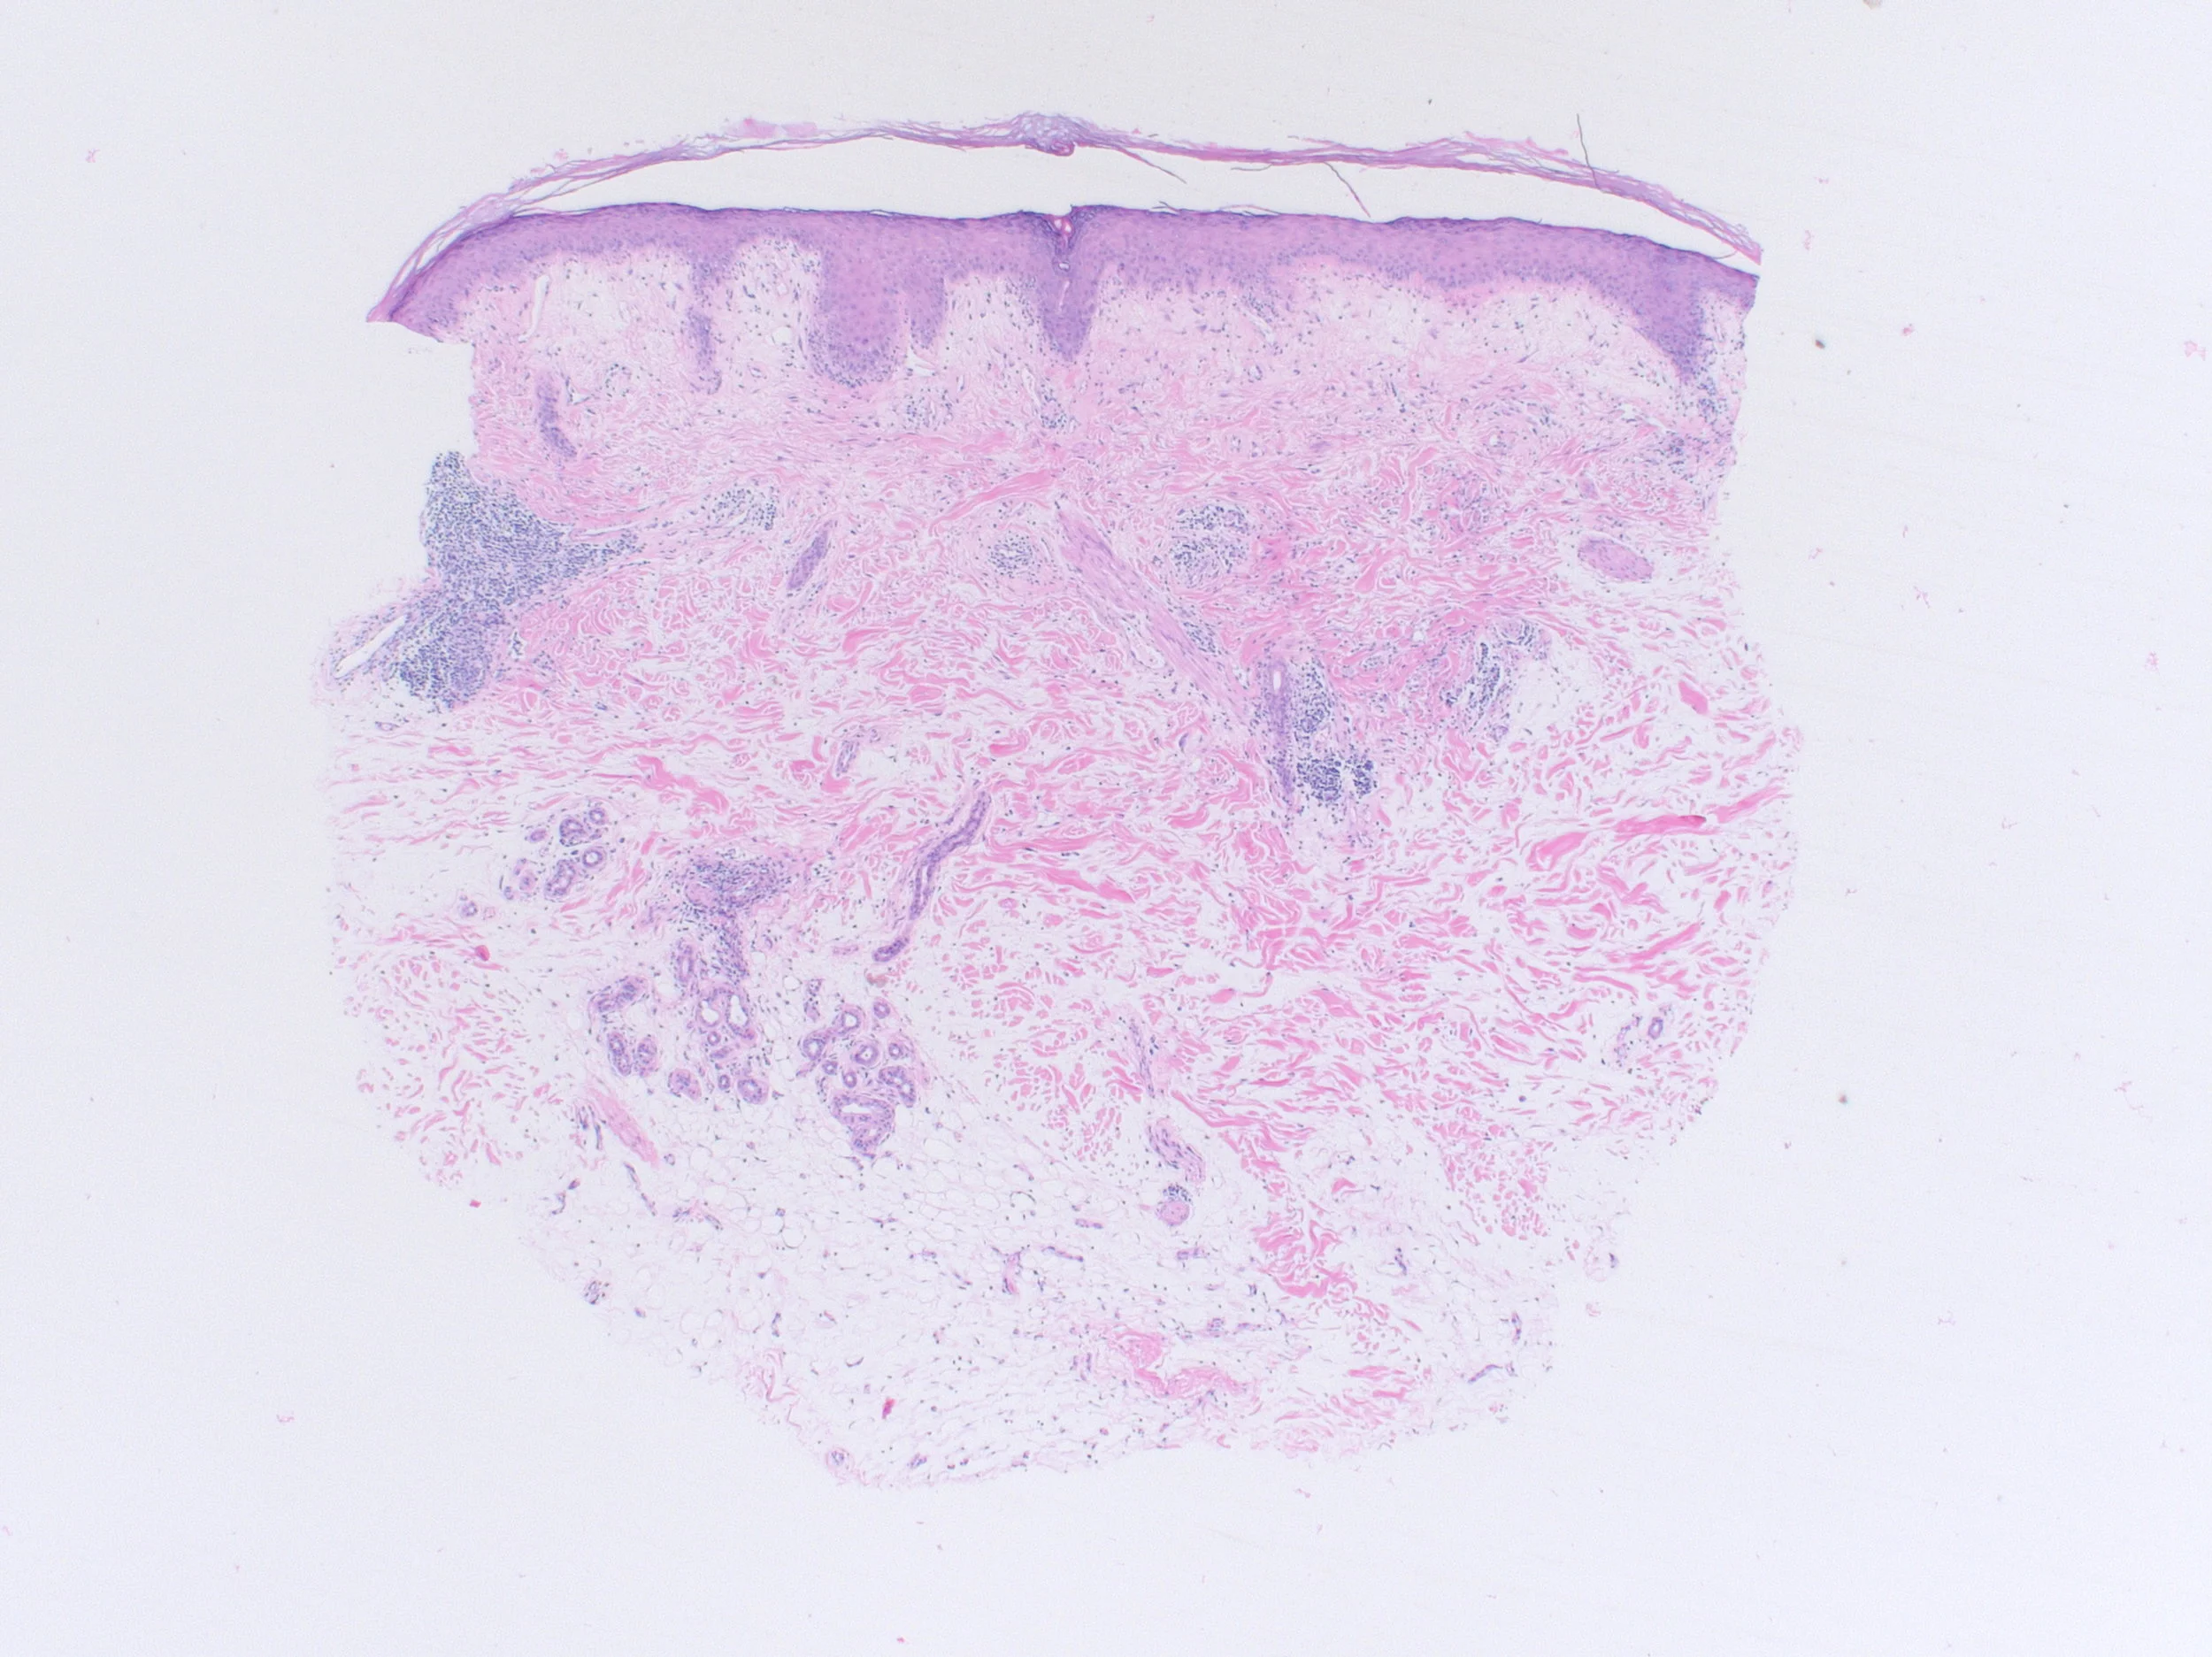

Left Shoulder Tip

Right Scalp